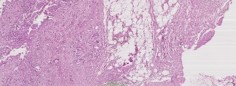

Материалы и методы. С 2017-го по 2021 г. в ФГБУ «РНЦРХТ им. академика А.М. Гранова» в протокол лечения нерезектабельной опухоли Клацкина с последующей трансплантацией печени было включено 6 пациентов. Неоадъювантное лечение включало эндобилиарную фотодинамическую терапию, регионарную и системную химиотерапию. Каждый метод применялся минимум трижды в течение четырех-пяти месяцев с радиологической оценкой и определением уровня Са19-9. Пациенты вносились в лист ожидания при снижении онкомаркера, отсутствии радиологических признаков прогрессии заболевания и без острого холангита. Реципиентам выполнялась лапароскопическая ревизия брюшной полости на предмет канцероматоза и оценка лимфоузлов печеночнодвенадцатиперстной связки со срочным морфологическим исследованием. При отсутствии внепеченочного распространения производилась трансплантация печени по классической методике с паракавальной, парааортальной и гепатодуоденальной лимфодиссекцией, билиодигестивным анастомозом на отключенной по Ру петле тонкой кишки. Операция выполнена трем пациентам, все из них – мужчины. Возраст колебался от 40 до 55 лет (средний – 48). Среднее время от начала лечения до трансплантации составило 9,3 месяца (от 6 до 14). Средний уровень Са19-9 на момент выполнения вмешательства составил 81,3 МЕ/мл (от 8 до 212).

Результаты. У трех пациентов, несмотря на лечение, отмечен рост уровня Са19-9 более чем в два раза в среднем за четыре месяца. У двух из них выявлена прогрессия заболевания согласно данным компьютерной томографии по RECIST. У одного пациента выявлен канцероматоз при диагностической лапароскопии. У трех пациентов Са19-9 снизился более чем в четыре раза. У двух из этих пациентов радиологически подтверждена стабилизация заболевания, у одного – частичный ответ. Один пациент умер через три года после трансплантации от сепсиса в исходе вторичного билиарного цирроза и билиарных абсцессов без признаков прогрессирования. Два пациента живы по настоящее время на протяжении 6 и 21 месяцев без признаков прогрессирования опухоли.